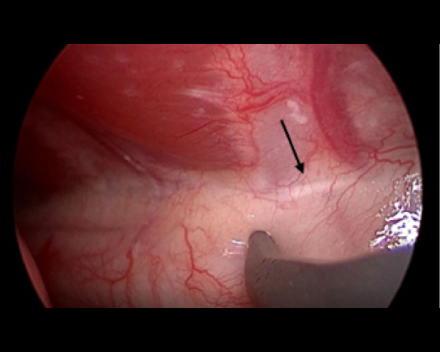

胸腔鏡で覗くと胸管がキレイに見えます(黒矢印)。

これを鉗子で丁寧に剥離していきます

反対側も同じように剥離していきます。

必ず、反対側の胸管も確認できるところまで剥離します。(黒矢印)